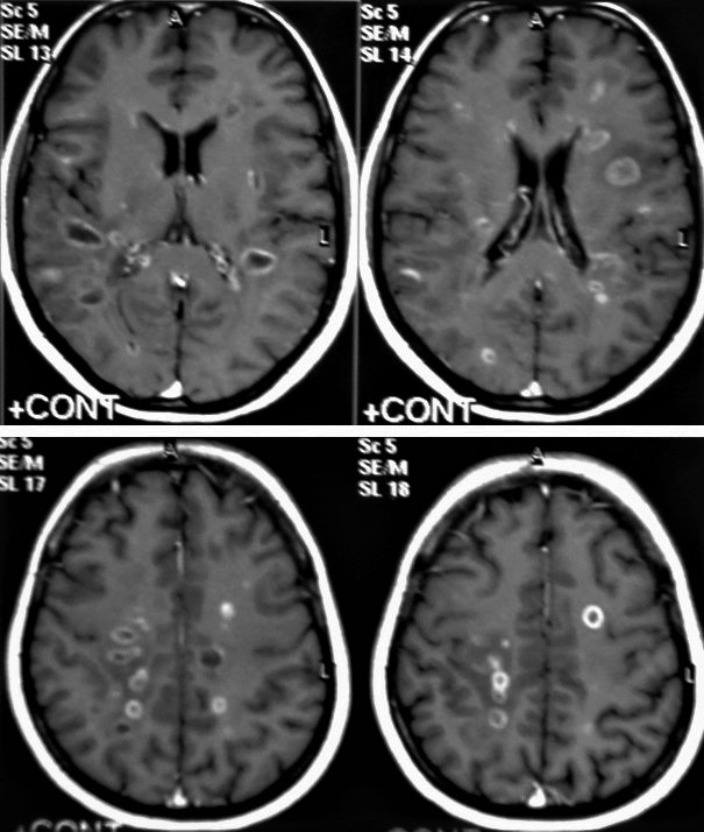

Figure 13. Multiple tuberculomas in an adult man. Selected MRI axial images post-contrast T1-weighted images show multiple small ring-enhancing lesions distributed in both cerebral hemispheres, with no significant surrounding cerebral edema, as is consistent with cerebral tuberculomas.